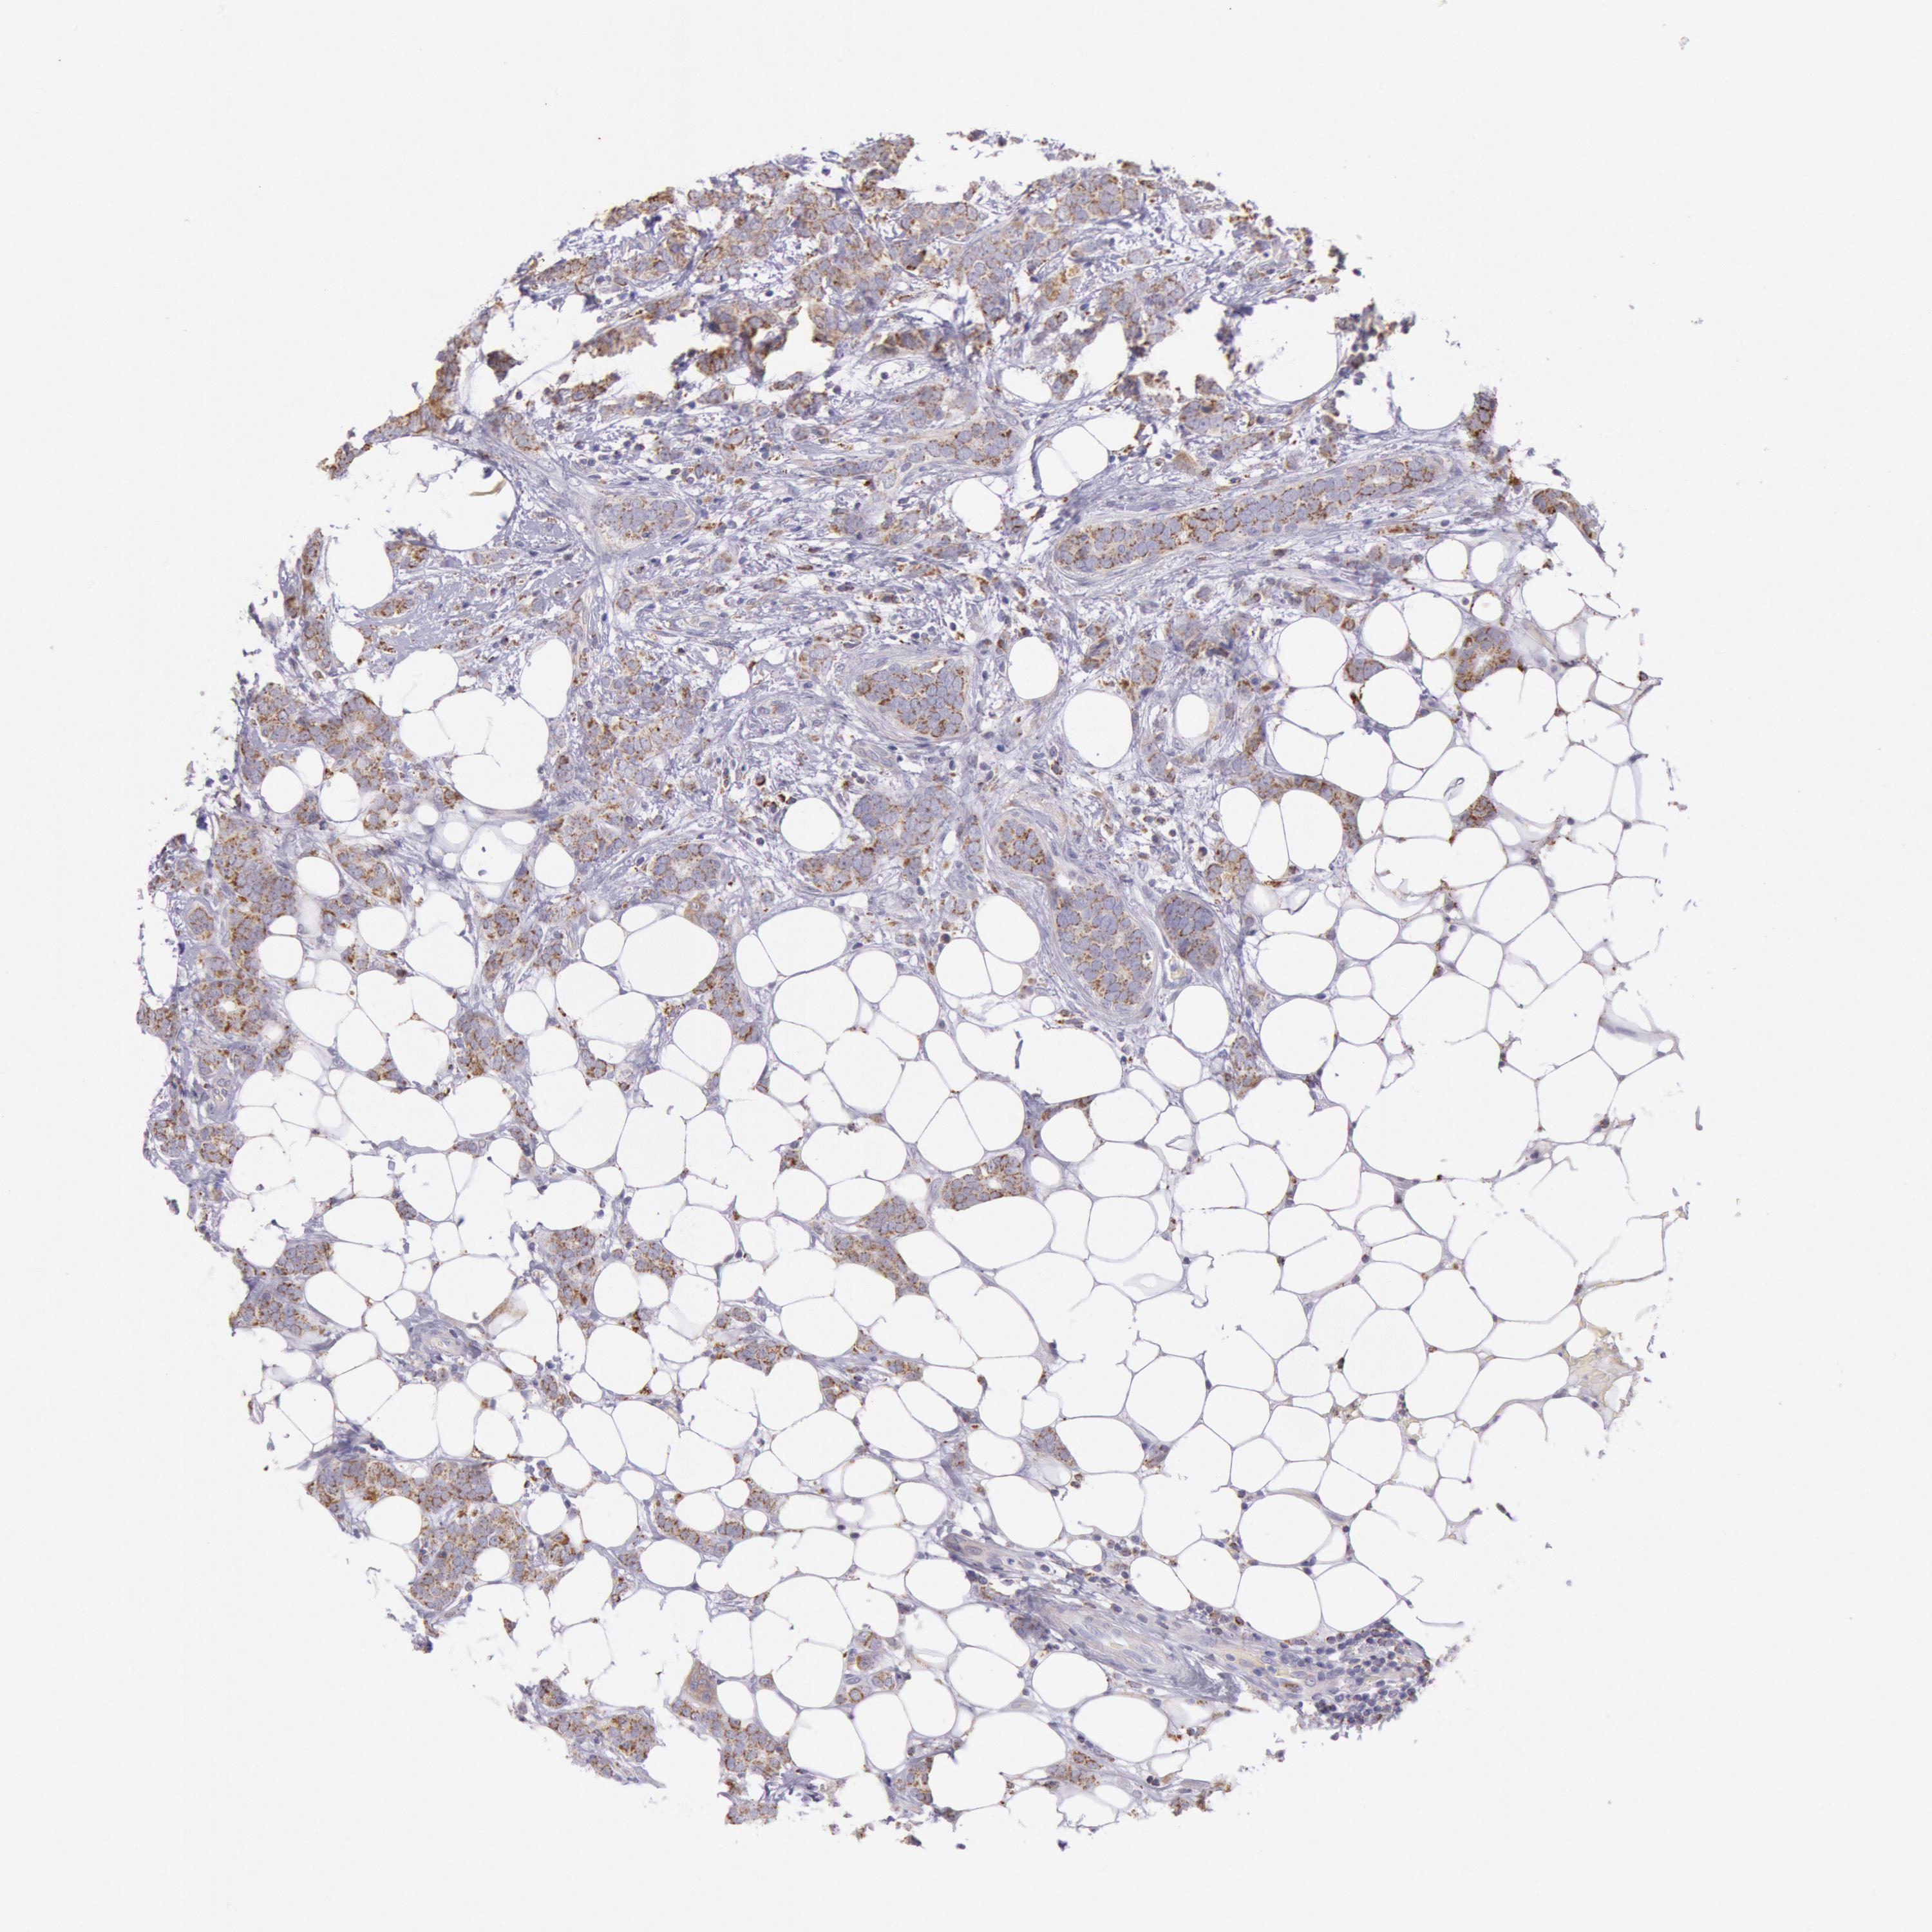

CANCER BREAST CANCER Show tissue menu

BRCA TCGA BRCA VALIDATION PROTEIN EXPRESSION